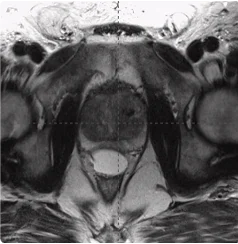

215 cc Prostate Post-MRI showing BioProtect Balloon Spacer, prostate, and rectum.

Post-MRI

Image courtesy of Dr. Shawn Zimberg, Radiation Oncologist.